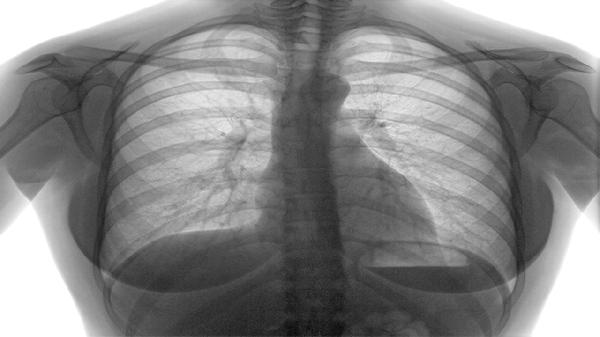

肺钙化灶是什么意思

肺钙化灶是肺部组织中出现钙盐沉积形成的局部病变,通常由感染、炎症或陈旧性损伤引起,多数情况下无需特殊治疗,但需定期复查。肺钙化灶的形成可能与结核、肺炎、寄生虫感染等疾病相关,也可能是肺部创伤或长期接触粉尘的结果。治疗上,若无症状且钙化灶稳定,仅需定期随访;若伴有其他症状或病灶变化,需进一步检查以排除恶性肿瘤或活动性感染。

1、感染因素:结核分枝杆菌感染是肺钙化灶的常见原因之一。结核病治愈后,肺部可能遗留钙化灶,这是机体免疫系统清除病原体后形成的瘢痕。其他感染如真菌、寄生虫也可能导致钙化,例如肺吸虫病或隐球菌感染。对于此类情况,通常无需治疗,但需通过胸部CT或X光定期监测钙化灶的变化。